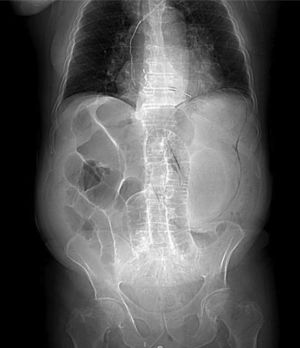

An 82-year-old man presented with bloating and generalized abdominal pain, accompanied by vomiting (dark in color, with an aspect of retention vomiting) and diarrheic stools. A plain abdominal x-ray (Fig. 1) showed air in the gastric wall and bowel segment dilation. An abdominal computed tomography (CT) scan was ordered (Fig. 2) that revealed intramural gas associated with gastric dilation, pneumoperitoneum (Fig. 3), and gas in the portal vein (Fig. 4). An exploratory laparotomy was performed, finding a distended stomach with gas bubbles in its serosa and no signs of transmural necrosis or perforation. Intraoperative gastroscopy identified ulcerated-necrotic mucosa with no spontaneous bleeding on the posterior surface, body, and greater curvature. Given those findings, no further surgical act was carried out. Lactobacillus jensenii was isolated in blood cultures and treated with meropenem + linezolid. The patient progressed favorably, with improvement in the control abdominal CT scan, and was released from the hospital. Emphysematous gastritis is a rare pathology produced by the translocation of gas-producing microorganisms in the walls of the stomach. The causal agent cannot be isolated in up to 42.4%1 of cases and there is a 60% mortality rate.2 CT is the diagnostic study of choice and is essential for making early diagnosis and implementing the vital support treatment with broad-spectrum antibiotics. Surgery is only required if there is no response to conservative treatment or in cases of severe sepsis or gastric perforation.3